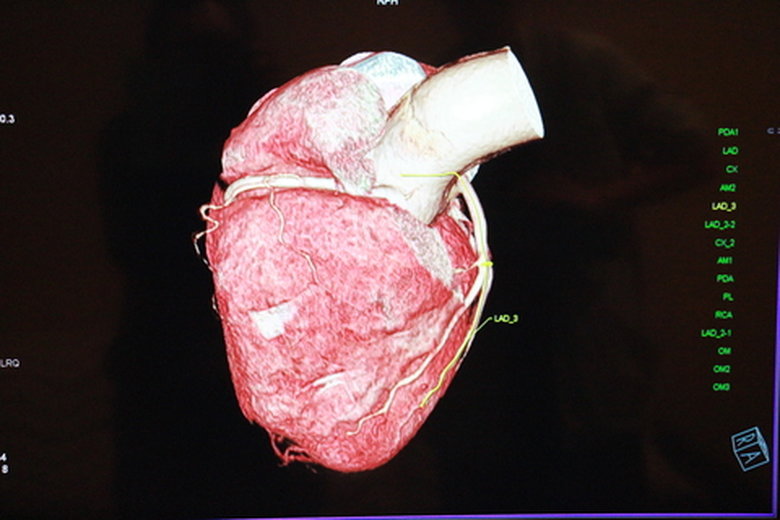

日前一名58歲男性患者突然間左手、左腳運動障礙,經過嘉基醫師診斷執行腦部MRI檢查發現腦部多處栓塞,透過心臟電腦斷層影像診斷,發現心臟左冠狀動脈瘻管的形成,由心臟內科醫師迅速執行心導管治療,使用金屬線圈將瘻管成功栓塞。

以往心臟的電腦斷層檢查,都以偵測冠狀動脈是否有狹窄及阻塞為主,目前透過新型高階電腦斷層掃瞄儀,已能精準的檢查出:如心臟的心室形成動脈瘤引起破裂、冠狀動脈瘻管的形成引起心臟不適等症狀,讓心臟專科醫師給予正確的治療。

嘉基影像醫學科科主任梁恒說明,一般電腦斷層掃描的切數代表儀器的探測針頭轉一圈得到的切面圖像張數,384切電腦斷層掃描之3D畫面可準確的評估冠狀動脈狹窄程度、粥樣斑塊結構及其鈣化之幅度、心肌梗塞的風險,同時減少輻射劑量曝露時間,且具有極短的快門時間可針對跳動的心臟擷取瞬間影像,大幅提升偵測病灶的能力。